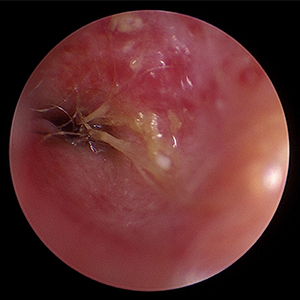

이도 내시경은 외이도부터 고막, 중이를 거쳐 내부를 고해상도로 관찰해 만성 외이염·이물·종양·고막 손상을 평가하고 세척, 조직검사까지 가능합니다.

이도 이물 제거 예시 이미지

이도이물제거